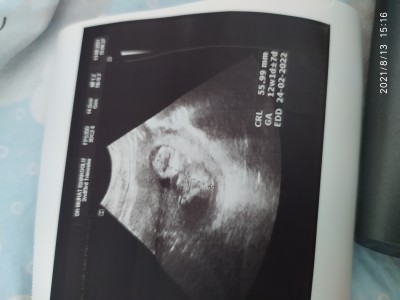

Doktor tahmin yapmadı sizce fikri olan varmi

Kız hissettim canım. Hayırlısı olsun inşallah

Bı tahminde bile bulunmadi çok snirlendm ya kemik yapsna bakarak tahminde bile bulunan var

Kac haftalik canim

Aa gördüm 12 hafta 1 günlük

Erkek hissettim ben canim